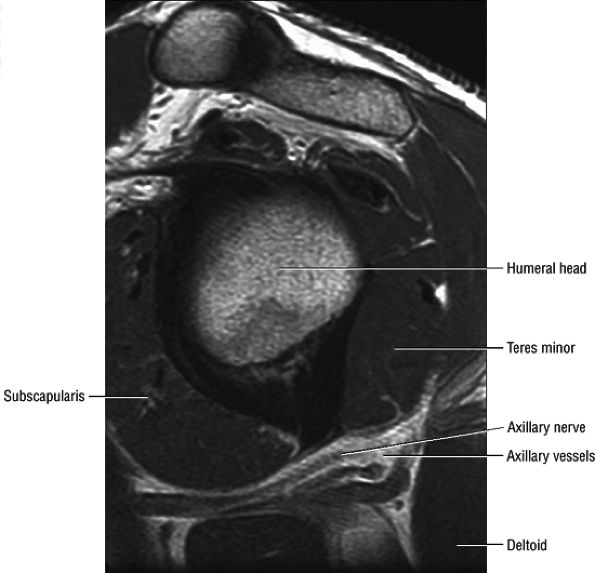

![]() |

FIGURE 12.6 ● Suprascapular nerve syndrome secondary to a suprascapular varix. Oblique coronal fat-suppressed T2-weighted (A) and axial PD-weighed (B) images demonstrate prominent suprascapular veins (arrow) within the suprascapular incisura and denervation edema of the infraspinatus (IS) muscle.